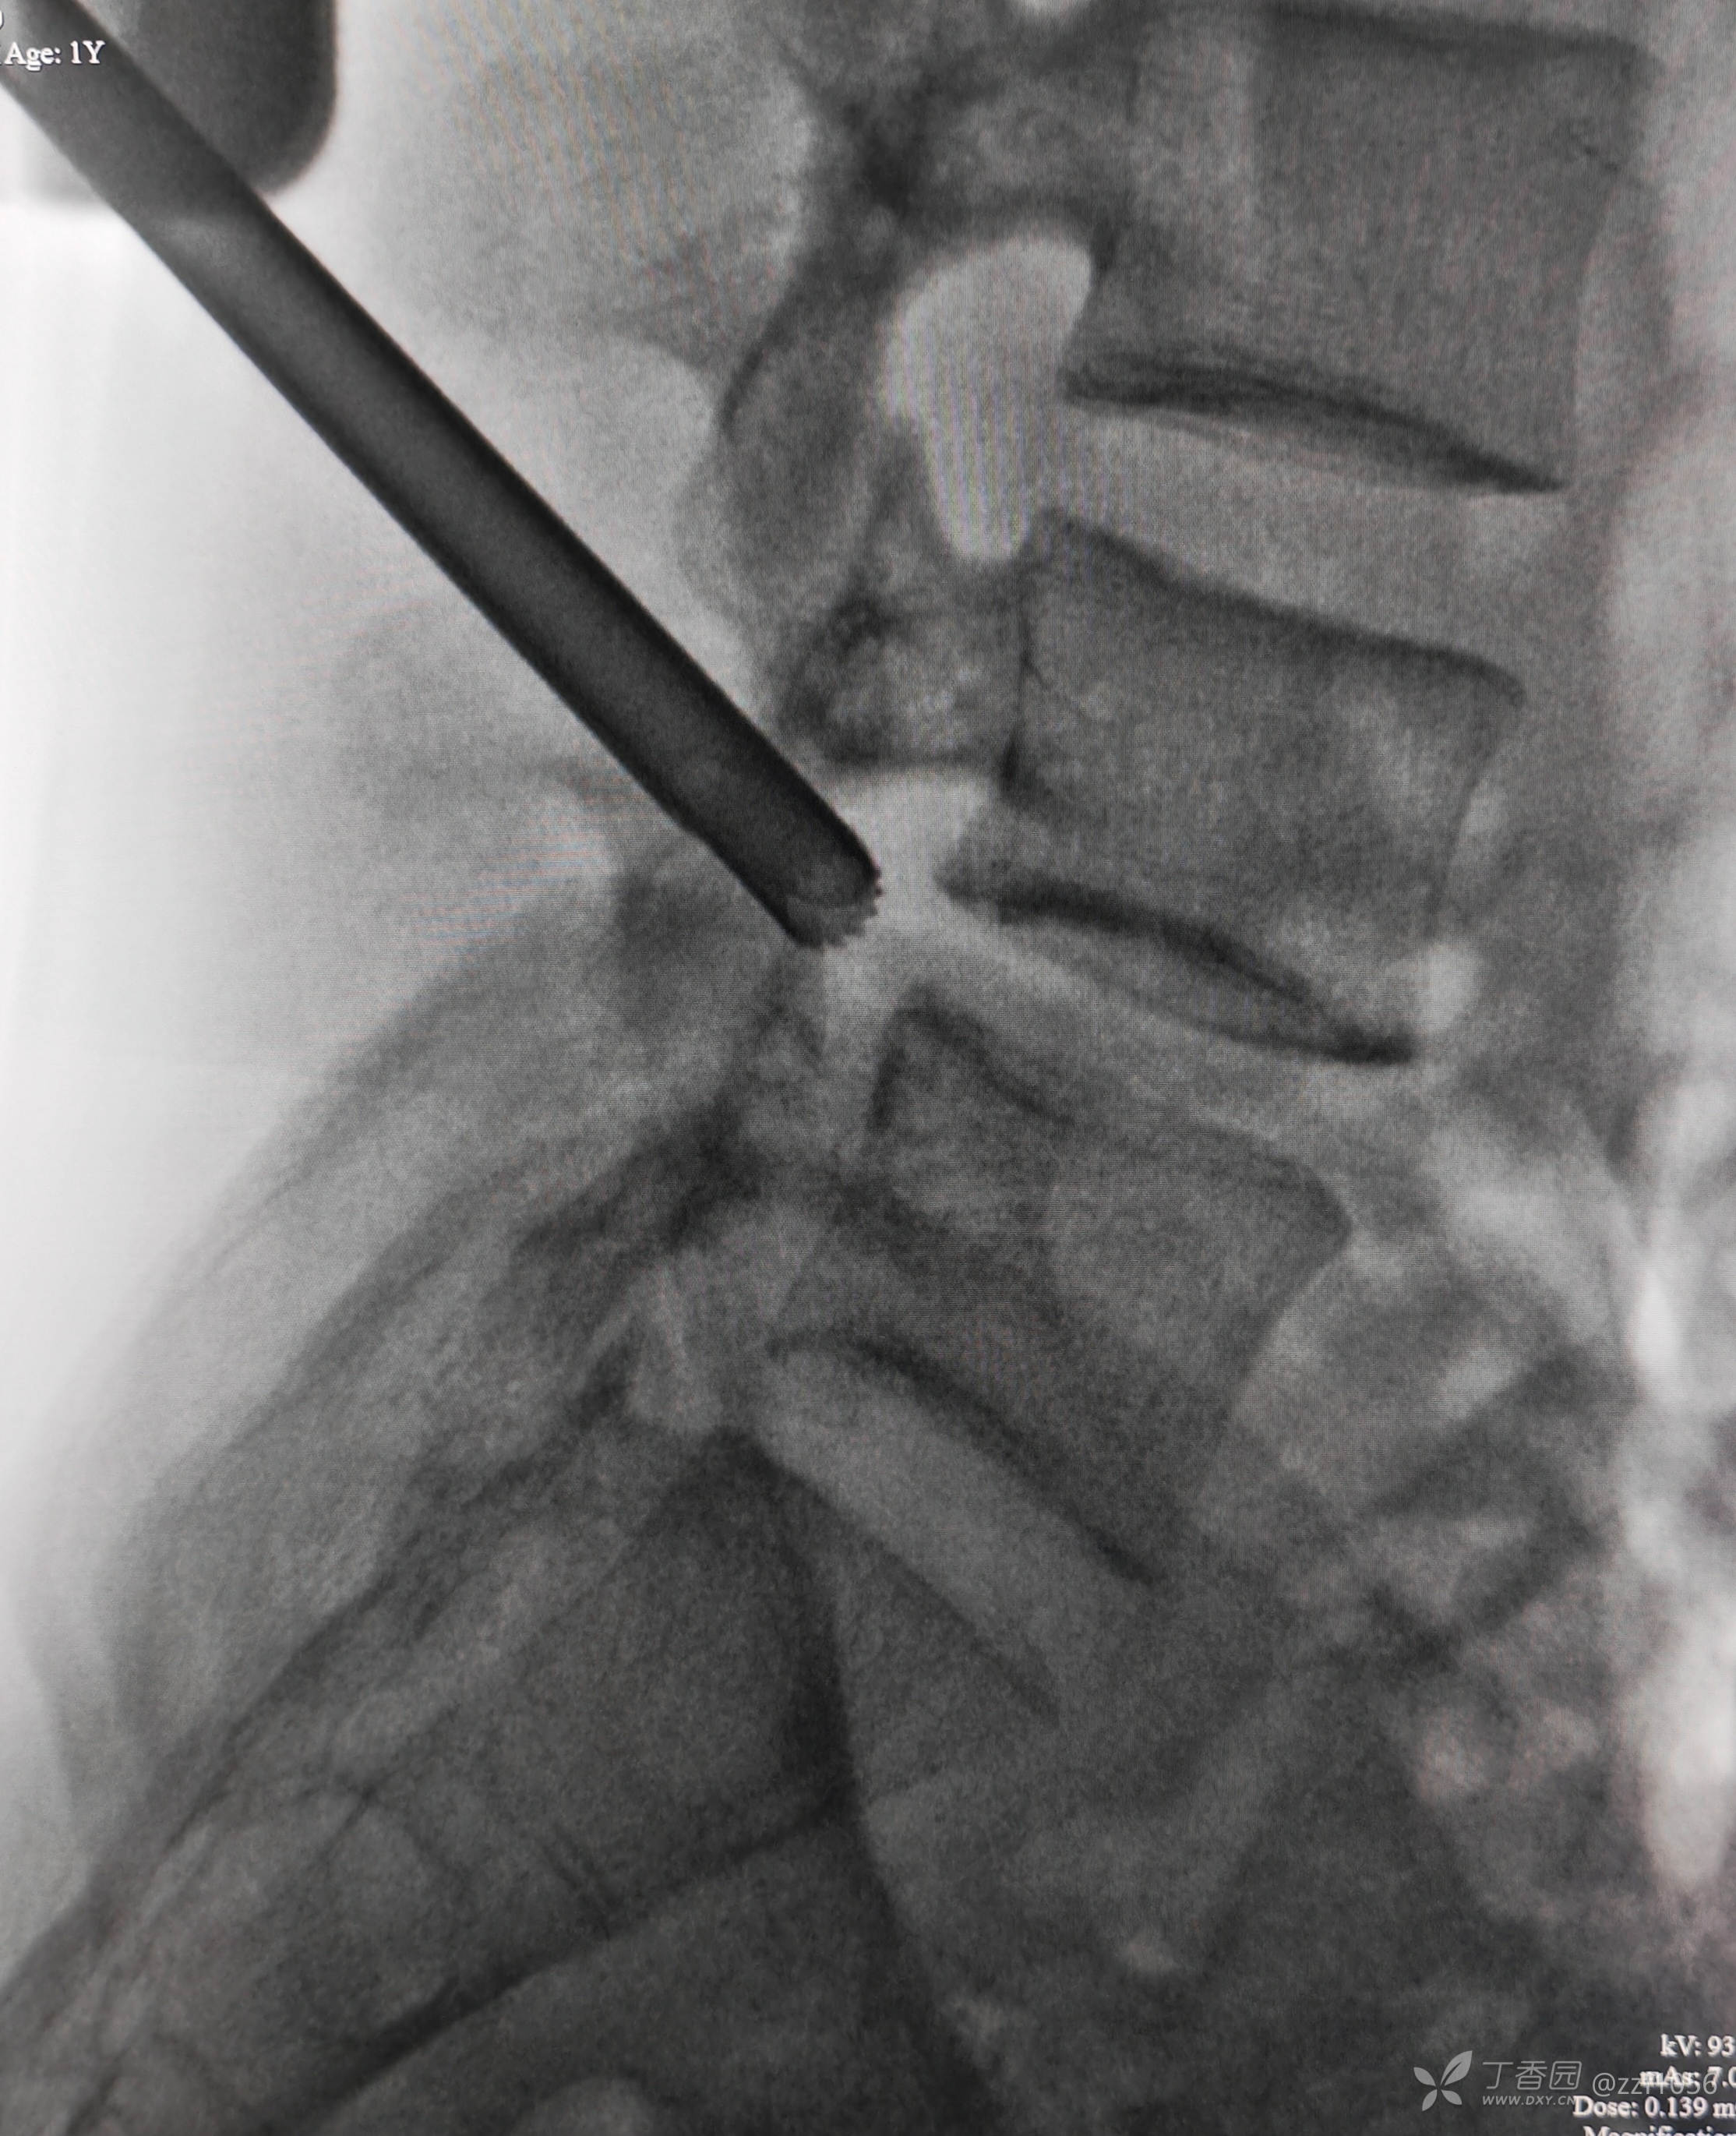

患者男,19岁,高三学生,左下肢疼痛半年,各种保守治疗无效

入院诊断:腰椎间盘突出症(L4/5)